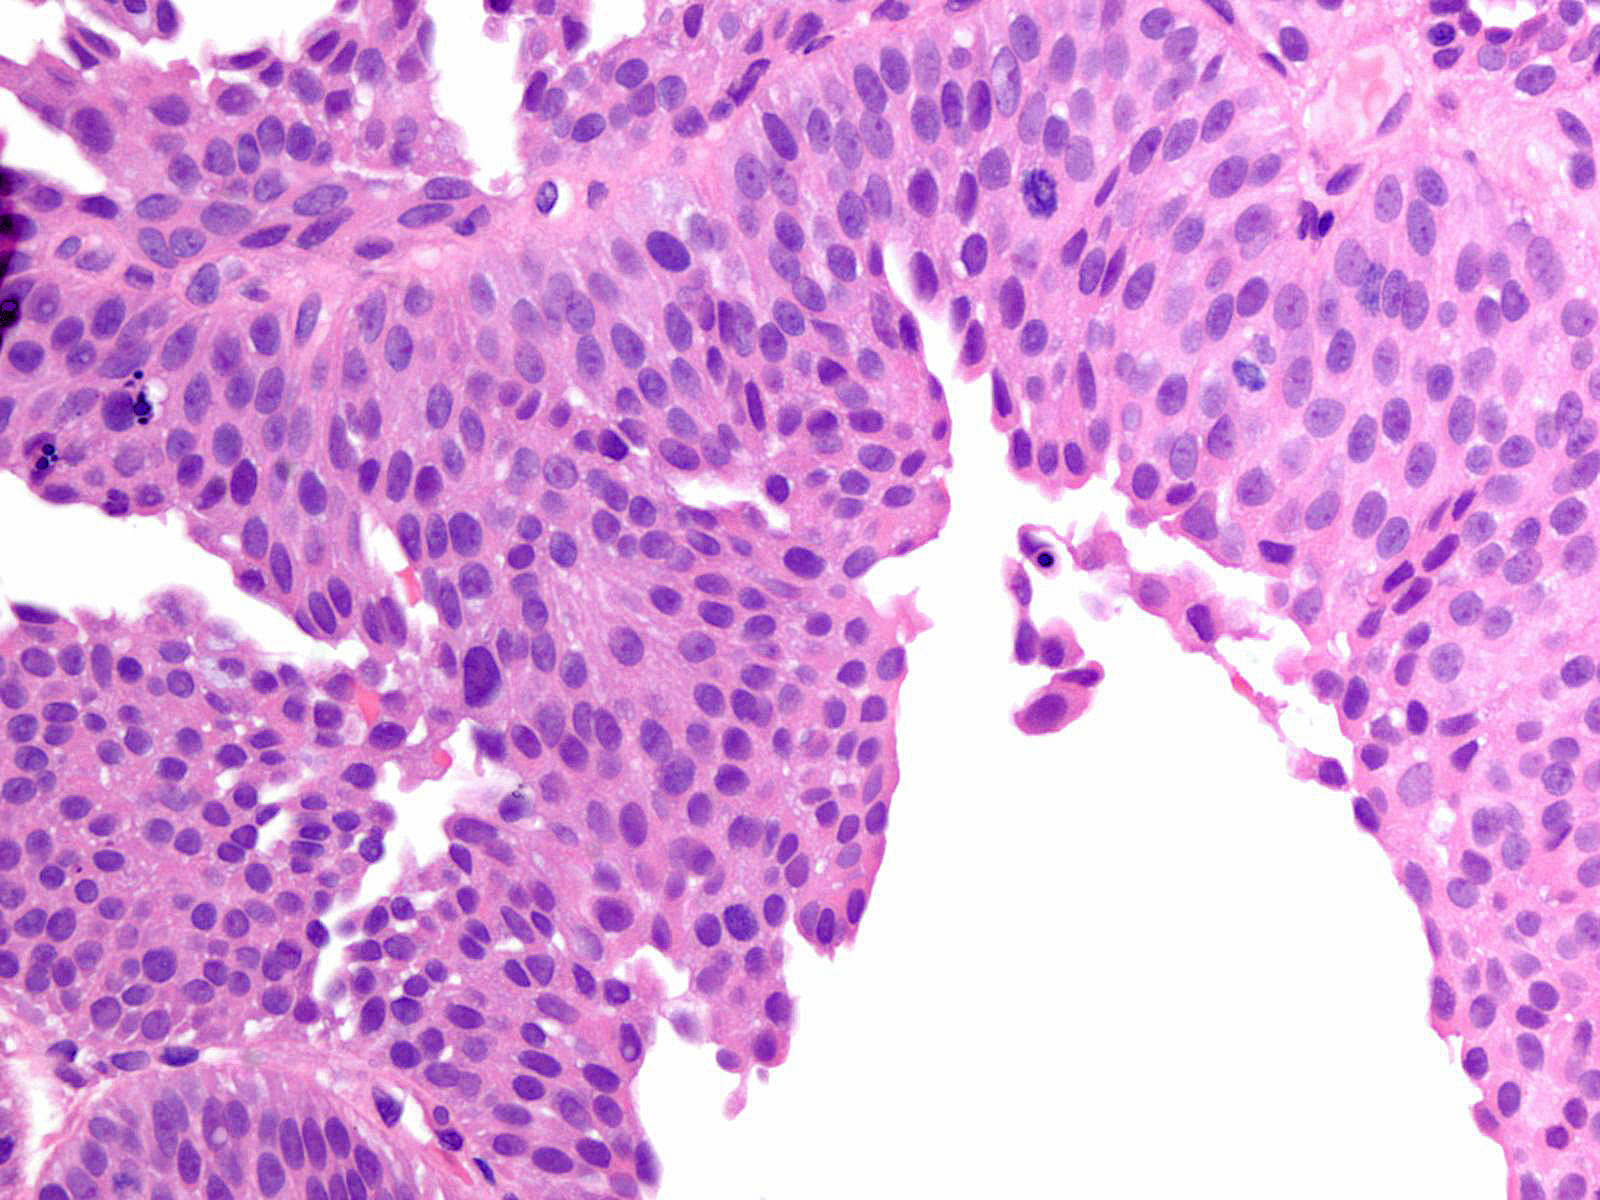

Bladder Papillary Lesions

Case ID: 149